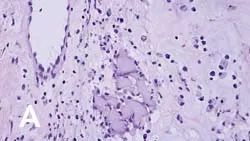

On histopathologic examination, transition zones are present from inflammation to sarcoma, and sarcoma foci are found in areas of granulomatous inflammation (Figure 1). It is hypothesized that postinjection inflammatory reactions, with the release of cytokines and growth factors, result in uncontrolled fibroblast and myofibroblast proliferation, leading to malignant transformation.

_Figure 1 (View larger image). Injection-site sarcoma associated with rabies vaccine administered 7 months prior to diagnosis. (A) Region showing granuloma formation and (B) sarcoma region with cells exhibiting criteria of malignancy, including bizarre mitotic figures (arrow).